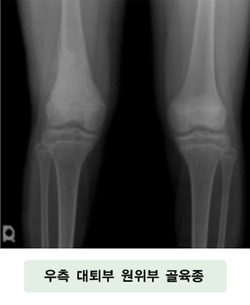

단순 방사선 사진 촬영은 악성 골종양을 진단하는데 가장 중요한 단계이며, 방법도 손쉽고 능률적입니다. 골 병변이 염증성 질환인지, 종양 계통이 양성 혹은 악성인지 어느 정도 구분할 수 있게 해주고, 종양의 위치, 크기, 모양을 관찰할 수 있습니다. 또한 통증은 다른 부위에서 방사된 것일 수 있으므로 인접 부위를 함께 관찰해야 합니다. 대부분의 악성 골종양은 경계가 불분명한 골 파괴와 특징적인 골막 반응 소견을 보입니다. 하지만 약 30-50%의 골 파괴가 일어날 경우에나 비로소 단순 방사선 사진 상에 나타나게 되므로 그 한계가 있습니다.

골육종은 골 증식이 왕성한데, 종양이 증식되어 근위 및 원위에 골막이 튀어나와 생기는 코드만 삼각 골막 반응을 보이거나, 많은 침골이 골 피질에 수직으로 배열하여 머리빗 모양을 나타내거나, 방사성으로 배열되어 햇살 모양의 골막 반응을 보이는 경우가 있습니다.

![]() [우측 대퇴골 원위부 골육종] |